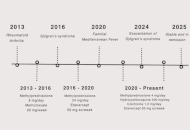

DOI: https://doi.org/10.37349/emed.2025.1001314 An unusual case of coexistence of Familial Mediterranean Fever with rheumatoid arthritis and Sjögren’s syndromeOpen AccessCase ReportWe report a rare case of a female patient with multiple rheumatological conditions. The patient initially presented with periodic, diffuse abdominal pain. This complaint was not fully investigated b [...] Read more.Fadi Altamimi ... Yasmeen AlabdallatPublished: April 27, 2025 Explor Med. 2025;6:1001313

An unusual case of coexistence of Familial Mediterranean Fever with rheumatoid arthritis and Sjögren’s syndromeOpen AccessCase ReportWe report a rare case of a female patient with multiple rheumatological conditions. The patient initially presented with periodic, diffuse abdominal pain. This complaint was not fully investigated b [...] Read more.Fadi Altamimi ... Yasmeen AlabdallatPublished: April 27, 2025 Explor Med. 2025;6:1001313